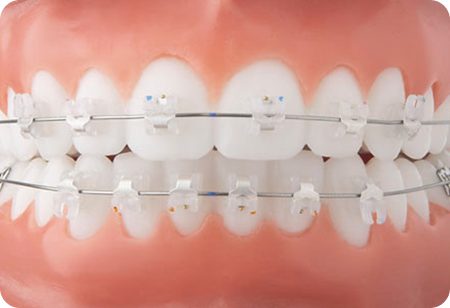

인비절라인(Invisalign)은 눈에 띄지않게 투명하게 제작된 교정 장치입니다.

치아 상태에 맞게 디지털 장비로 맞춤 설계된 투명 교정 장치를 주기적으로 교체하며 치아를 서서히 이동시키는 방식으로 진행됩니다.

기존의 금속 교정 장치와 달리 뛰어난 심미성으로

티나지 않는 교정을 원하시는 경우 적합하며 탈부착이 가능하여 위생관리가 편안합니다.